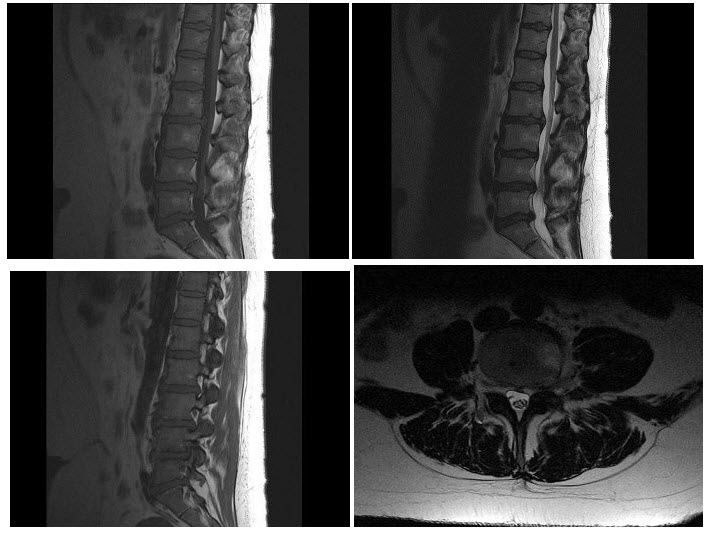

D.畸形性骨炎